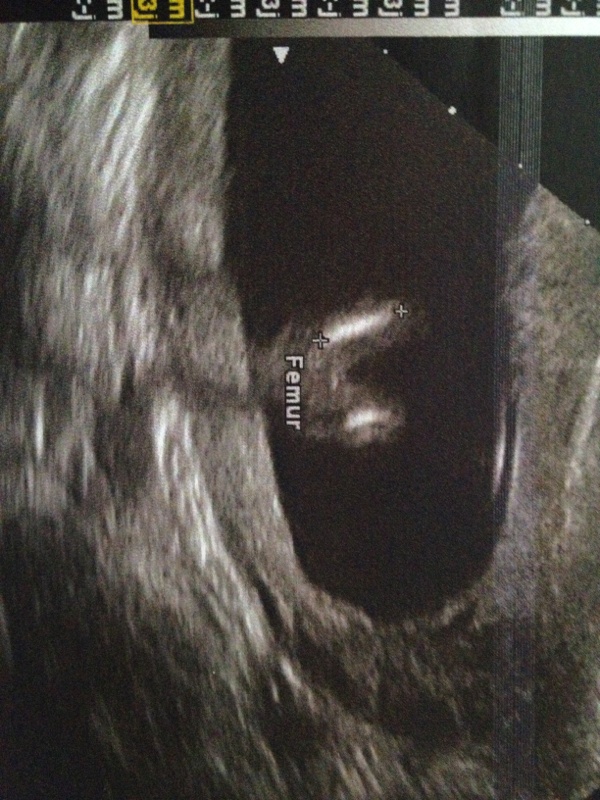

louloute26 a dit:Coucou les minettes!! Cette aprem a 15h15 je vais faire mon echo!!! J'espère que tout ce passe bien et j'espere que je pourrai découvrir le sexe!! Hihihi j'suis pressé!!!!